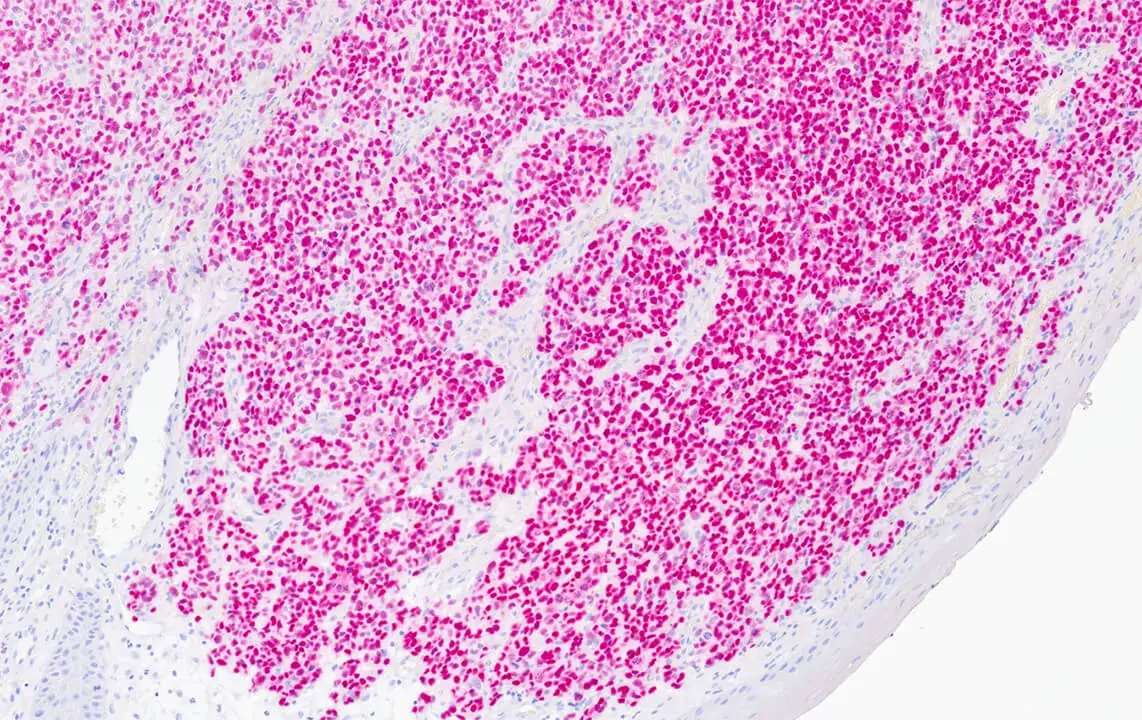

Melanoma: DAB staining of SOX10. Clone SOX10/991.

SOX10 is a nuclear transcription factor in the SOX (SRY Box) family of proteins, that plays an important role in neural crest development among other functions. As such it is expressed in cells of neural crest origin, including melanocytes and Schwann cells. It has been shown to be a sensitive and specific marker to aid in the diagnosis of melanoma, including spindle and desmoplastic subtypes, as well as a specific marker to aid in the differentiation of Malignant Peripheral Nerve Sheath Tumor (MPNST) from synovial sarcoma.